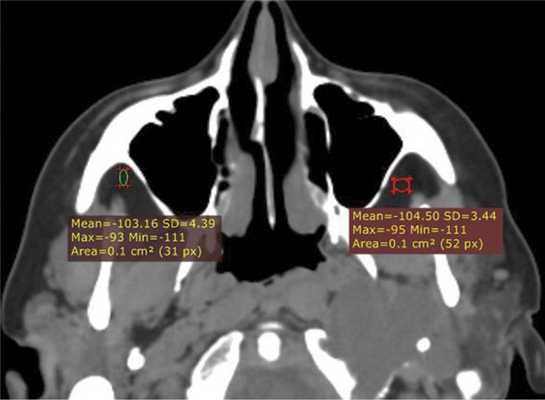

В костном режиме программы просмотра изображений утолщение костных стенок верхнечелюстной пазухи определялось в 21% случаев (рис. 2, 3), что указывает на хронический характер воспаления. «Оптический эффект» в мягкотканном режиме программы просмотра диагностических изображений определялся у 30,7% больных, что указывает на вовлечение надкостницы.

Рис. 2. Рентгеновская компьютерная томограмма околоносовых пазух. Аксиальная проекция, костное окно.

Рис. 3. Рентгеновская компьютерная томограмма околоносовых пазух. Аксиальная проекция, костное окно.

При воспалительных изменениях в ретроантральной жировой клетчатке верхнечелюстной пазухи на РКТ повышаются денситометрические значения ее плотности [10]. При одностороннем процессе отмечается выраженная асимметричность значений плотностей (рис. 4).

Рис. 4. Рентгеновская компьютерная томограмма околоносовых пазух. Аксиальная проекция, костное окно.

В 63,2% случаев на РКТ при выявлении одонтогенного верхнечелюстного синусита отмечалось уплотнение жировой клетчатки. Исследователи связывают это с переходом воспалительной инфильтрации пристеночной слизистой по периваскулярным пространствам к ретромаксиллярной клетчатке [7, 11, 12].